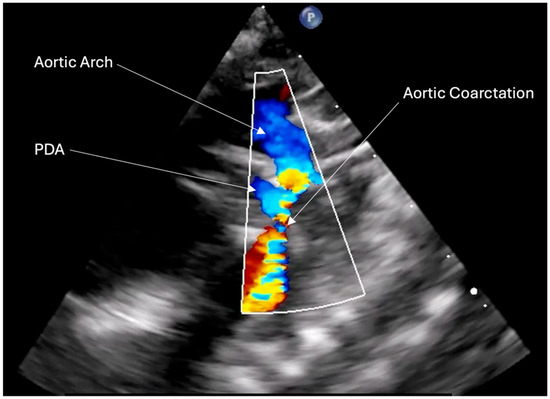

2. Case Presentation